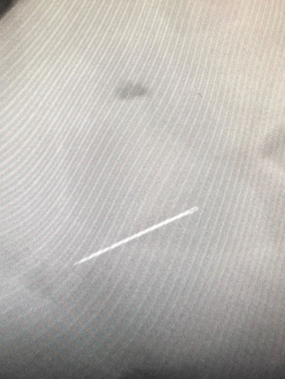

・レントゲン検査 異物の有無や腸の状態を確認 (異物内容によってはレントゲンにうつらないこともあります)

・造影レントゲン検査 (異物の位置やうっ滞、閉塞を確認)